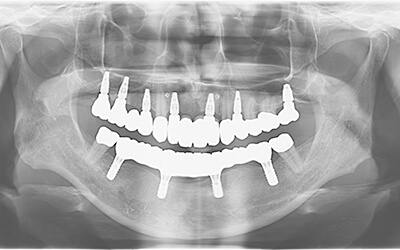

【歯周病で多数歯欠損②】とにかく入れ歯をやめたい!上オールオン6・下オールオン4の患者様

患者さま情報:40代 男性

治療期間:11ヶ月

治療費:5,082,000円(税込)

リスク:骨が足りない場合は骨を足す骨造成が必要です。

副作用:手術により腫れや痛みを伴う場合があります。

before

after